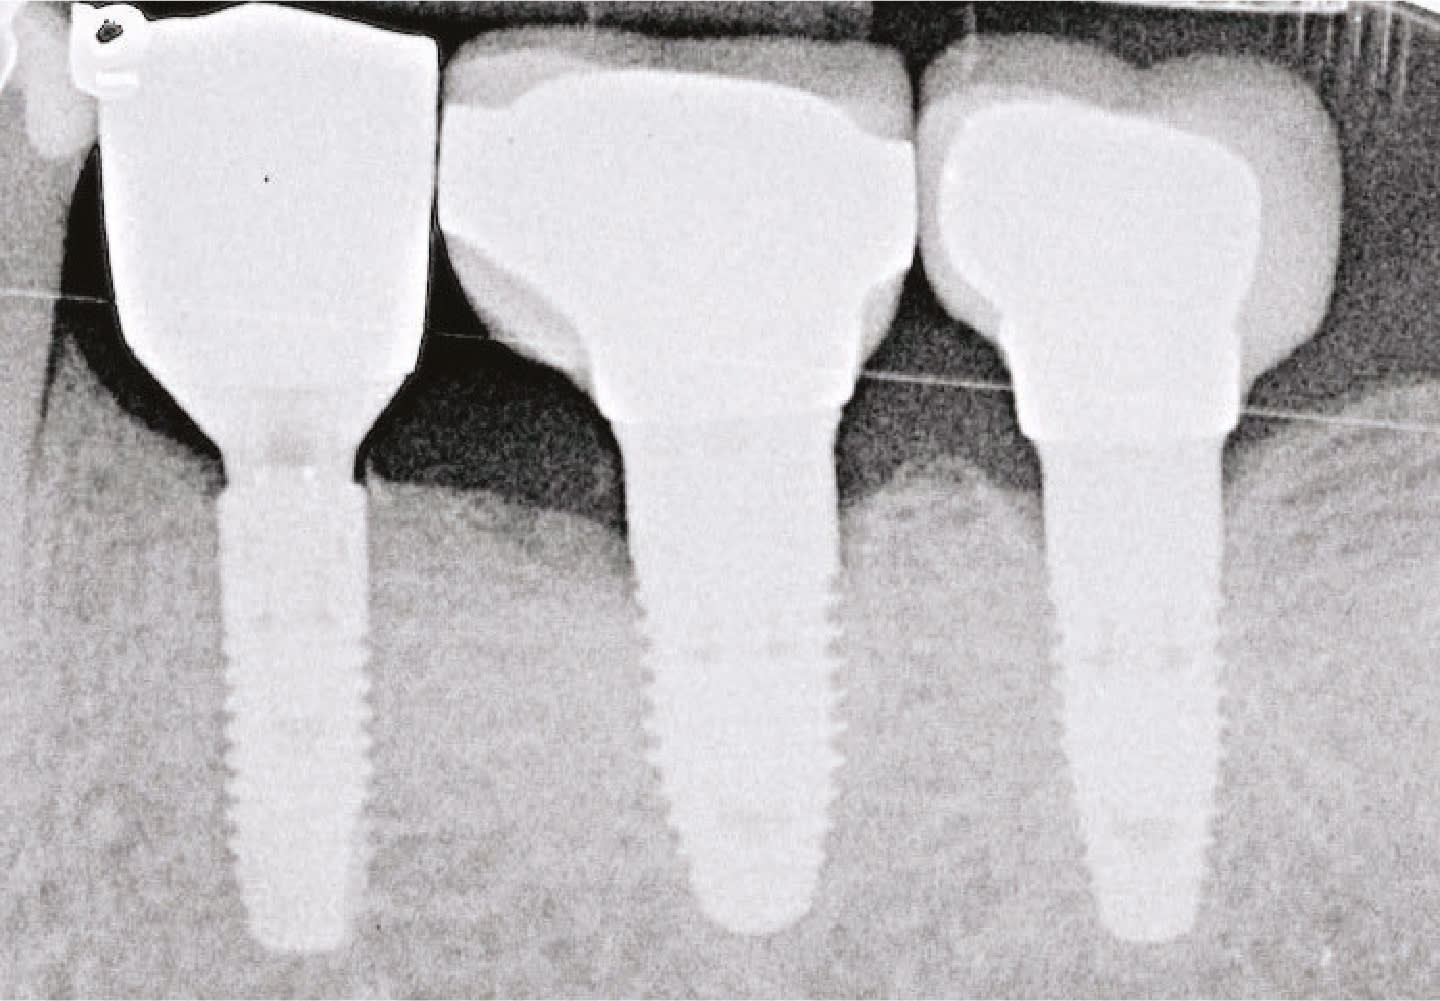

Dr. Wong also uses the PerioLase MVP-7 for the LAPIP™ protocol to treat peri-implantitis and save ailing and failing implants. In addition, the laser’s exclusive BLAST™ protocol for peri-implantitis and osseointegration is designed for long-term implant success.

- The laser is also used to perform the LAPIP™ protocol for the treatment of peri-implantitis, providing a minimally invasive option for addressing infection around dental implants.